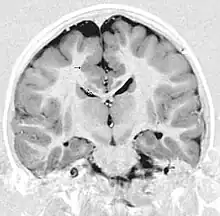

| This child presented with seizures. The coronal true inversion recovery sequence shows thickened and disordered cortex in superior frontal and cingulate gyri bilaterally (arrow). There are small convolutions visible at the corticomedullary junction. The appearance is that of cortical dysplasia, with polymicrogyria more likely than pachygyria due to the small convolutions visible. There are also small foci of grey matter signal in the corpus callosum, deep to the dysplastic cortex (double arrows). These probably represent areas of grey matter heterotopia. | |